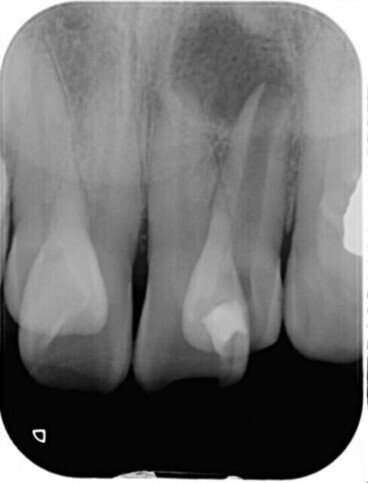

根管の状態によってはMTAセメントの使用

強い殺菌作用と高い封鎖性を持つMTAセメントを、症例に応じて使用します。難治性の根管や根の先に病変がある場合でも、治癒を促す効果が期待できます。

破折ファイル(根管内異物の除去)

過去の治療で根管内に器具が折れて残っている場合でも、マイクロスコープを用いて可能な限り安全に除去を行います。歯を残すための選択肢を広げます。